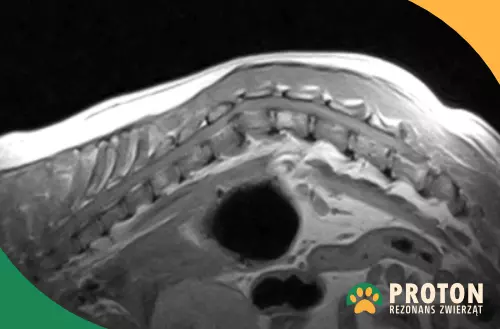

W trakcie badania lekarz ocenia struktury kostne (trzony i łuki kręgów, wyrostki), krążki międzykręgowe, więzadła oraz struktury nerwowe (rdzeń kręgowy wraz z wychodzącymi korzeniami nerwowymi). W badaniu RM widoczne jest ponadto umięśnienie okolicy kręgosłupa.

Lekarz analizuje kolejne przekroje kręgosłupa w kilku płaszczyznach, poszukując nieprawidłowych zmian, które mogą być odpowiedzialne za obecność objawów obserwowanych u zwierzaka.

Obraz RM kręgosłupa psa